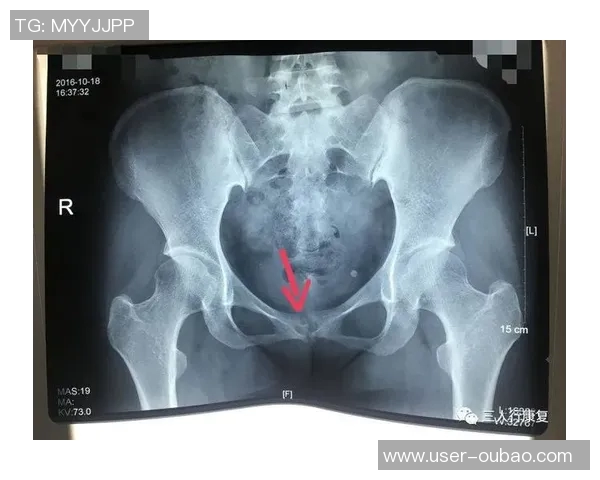

尼科·威廉姆斯是一名备受瞩目的年轻球员,他在比赛中表现出色,为球队贡献了许多关键进球。然而,在一次重要比赛中,他不幸遭遇了耻骨炎。这种疾病给他的训练和比赛造成了严重影响,让他不得不面对漫长而艰难的恢复过程。

初期,尼科并没有意识到自己的伤势有多严重。他依旧坚持参加训练,但随着时间推移,他逐渐感受到身体的不适。经过专业医生的检查后,他被确诊为耻骨炎,这让他深感沮丧,因为这意味着他需要停下脚步,进行长时间的康复治疗。